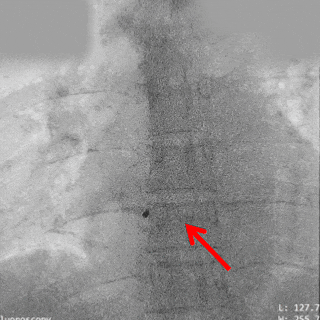

释放氧化膜封堵器左右盘面

牵拉试验封堵器稳定

释放封堵器

封堵器稳固夹持

本例为一例房间隔缺损(ASD)患者,术前彩超显示房间隔中部回声缺失,四腔心观缺损间距约1.08 cm,彩色多普勒可见左向右分流,流速曲线呈双期湍流,术前复测缺损为1.2 cm,经综合考虑,最终植入22规格MemoCarna氧化膜ASD封堵器。术中应用PannaWire®多功能导丝实现高效过隔,该导丝凭借其独特的梭形头端与分段结构设计,过程充当“泥鳅导丝+加硬导丝”功能,一丝多用,实现零交换操作,显著减少器械交换步骤,提升了手术效率;同时,梭形头端可固定在肺静脉处,避免出现导丝脱出导致重新建立输送轨道。封堵器展开后形态良好,稳定夹持于房间隔两侧,无残余分流。该病例充分验证了PannaWire®多功能导丝在简化ASD封堵流程、提升操作安全性及效率方面的临床优势。